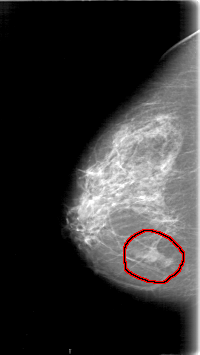

D_4064_1.RIGHT_CC

FILE: D_4064_1.RIGHT_CC.OVERLAY

TOTAL_ABNORMALITIES 1

ABNORMALITY 1

LESION_TYPE MASS SHAPE LOBULATED MARGINS ILL_DEFINED

ASSESSMENT 0

SUBTLETY 5

PATHOLOGY BENIGN

TOTAL_OUTLINES 1

BOUNDARY